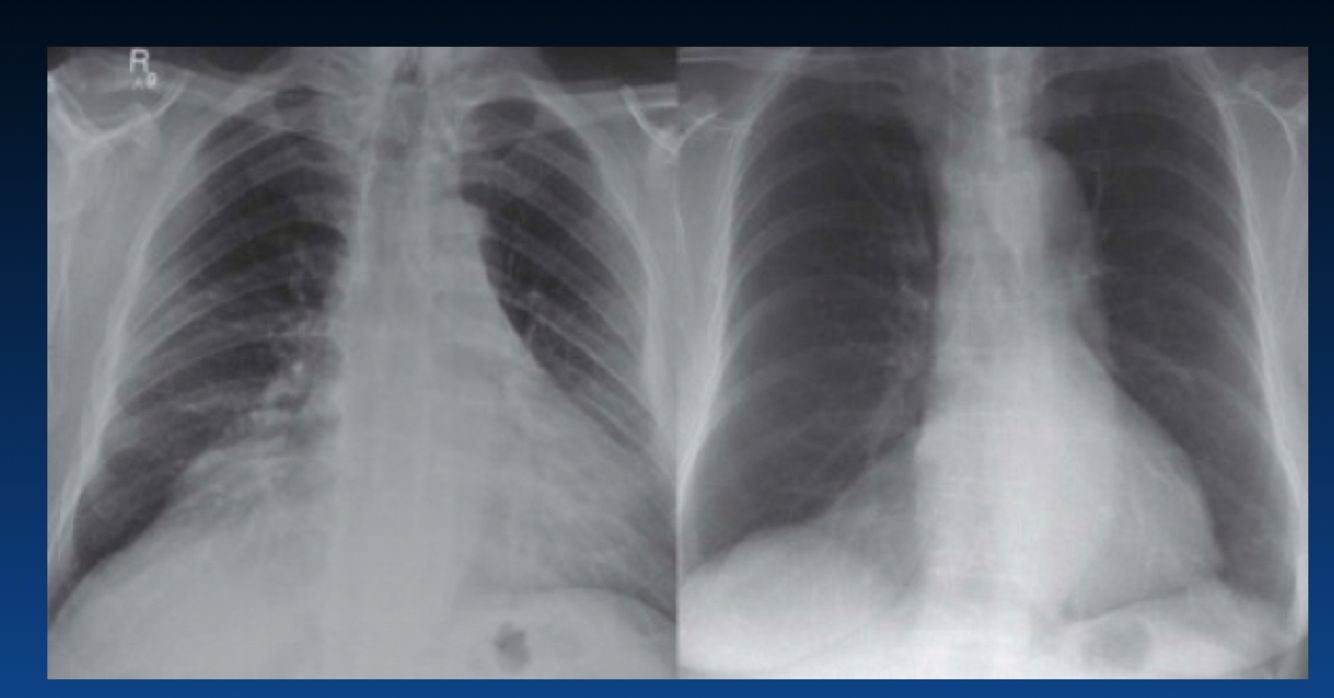

This does not show a real increase CTR. Why?

You can tell an expiration by the height of diaphragm as well as counting the ribs (the right only shows 4 ribs). You should see 6 or 7 ribs.